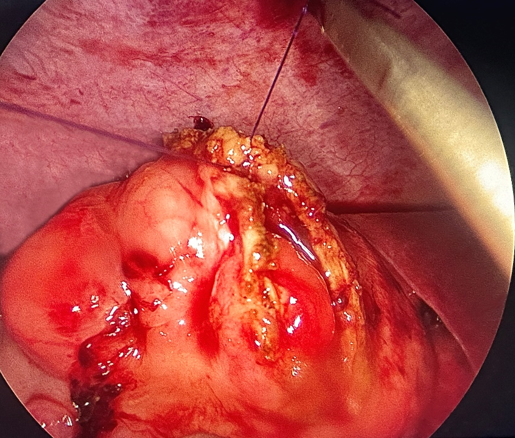

Sau khi cắt toàn bộ khối u,

các bác sĩ đã tiến hành khâu lại chỗ mở manh tràng bằng nội soi, (Hình 4). Sau

phẫu thuật, sức khỏe bệnh nhân diễn biến thuận lợi, hết đau bụng, ăn được,

không bị lồng ruột tái phát.

Hình

4: Khâu lại manh tràng bằng nội soi sau khi cắt u manh tràng